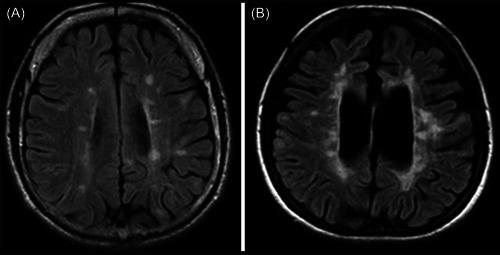

Comparison of recent updates in genetics, immunology, biomarkers, and neuroimaging of primary-progressive and relapsing-remitting multiple sclerosis and the role of ocrelizumab in the management of their refractory cases.

Primary-progressive multiple sclerosis (PPMS) and relapsing-remitting multiple sclerosis (RRMS) are two frequent multiple sclerosis (MS) subtypes that involve 10%-15% of patients. PPMS progresses slowly and is diagnosed later in life. Both subtypes are influenced by genetic and environmental factors such as smoking, obesity, and vitamin D insufficiency. Although there is no cure, ocrelizumab can reduce symptoms and delay disease development. RRMS is an autoimmune disease that causes inflammation, demyelination, and disability. Early detection, therapy, and lifestyle changes are critical. This study delves into genetics, immunology, biomarkers, neuroimaging, and the usefulness of ocrelizumab in the treatment of refractory patients of PPMS.